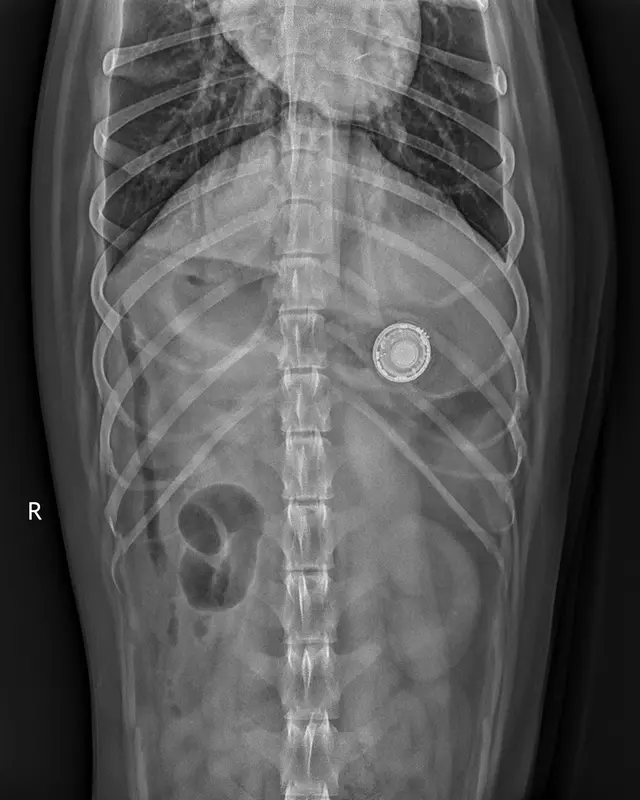

Luna, 6-miesięczny szczeniak, została zabrana do weterynarza po tym, jak zjadła urządzenie. Weterynarz chciał nawet operować, ale na szczęście po chwili zawieszka wypadła naturalnie.